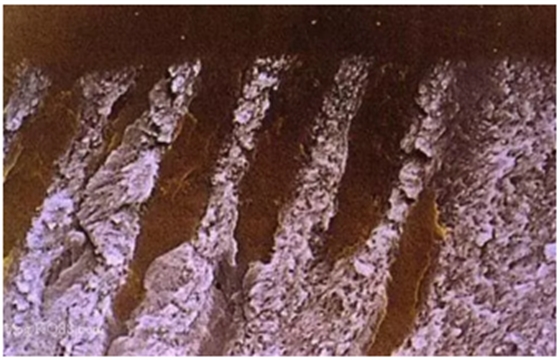

下面這幾副圖仍然是引自《牙體修復(fù)學(xué)新進展》一書,對我們理解全酸蝕后牙本質(zhì)濕粘結(jié)會有所幫助:

詳細了解自酸蝕、全酸蝕

圖示牙本質(zhì)全酸蝕后管間牙本質(zhì)膠原纖維網(wǎng)充分暴露

放大的膠原纖維網(wǎng)(放大倍數(shù)2000)